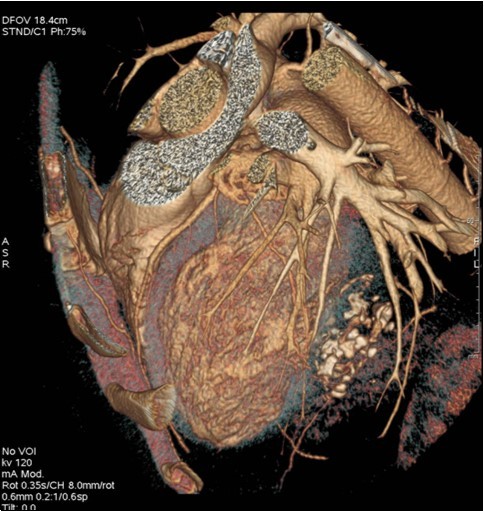

The 64-slice computed tomography (CT) showed a left ventricle intra-myocardial mass of tissue density (25 HU), not enhancing after injection of contrast, and containing multiple central and peripheral arciform calcifications (Figure 3,Figure 4,and Figure 5).

Figure 5.Coroscanner with three-dimensional reconstruction: intra-myocardial mass of left ventricle with multiple calcifications.